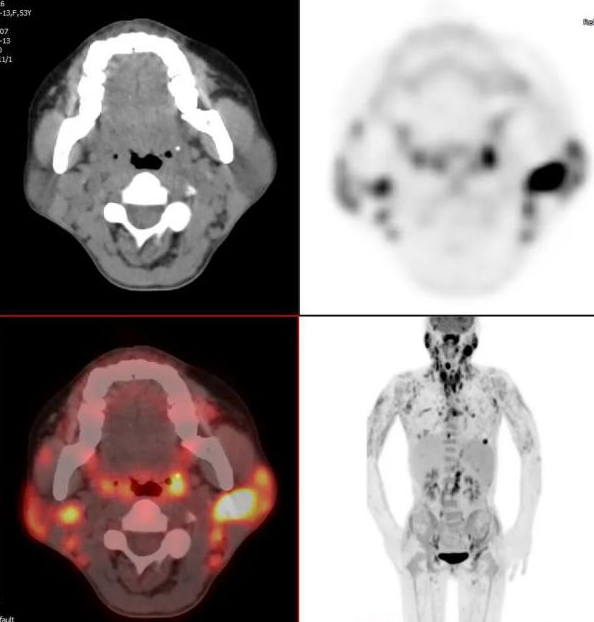

右侧扁桃体、左侧颈部及多处骨髓代谢增高灶(Ⅳ期)

双侧颈部、腋窝及纵隔、腹膜后多发淋巴结代谢增高(Ⅲ期)